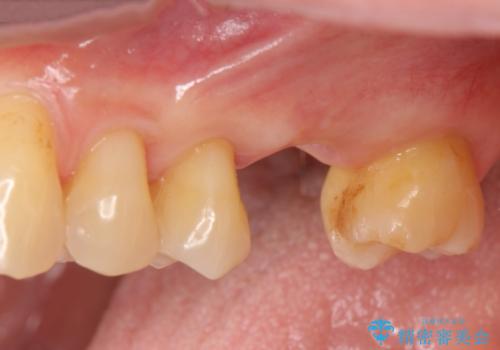

[遊離歯肉移植] インプラント周囲の角化歯肉の獲得

![[遊離歯肉移植] インプラント周囲の角化歯肉の獲得の症例 治療前](https://seimitsushinbi.jp/wp/wp-content/uploads/2020/01/ed937e86f21629e18e8c1dc62b85d1a9-500x350.jpg?v=1580303875)